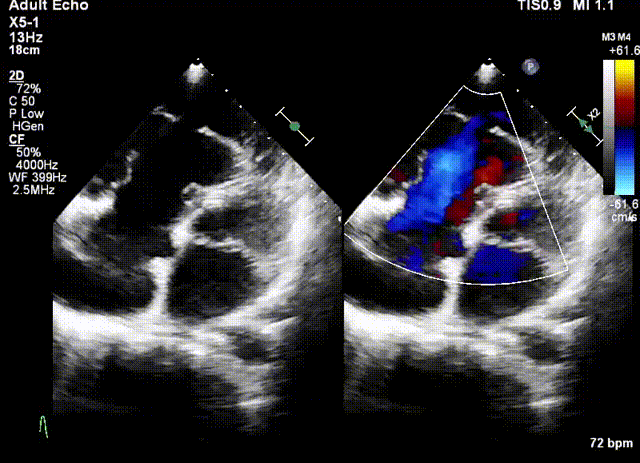

術(shù)前超聲

該例患者為79歲女性,NYHAⅢ級(jí),心衰癥狀顯著,藥物(大劑量利尿劑)治療9個(gè)月后仍出現(xiàn)頑固性踝關(guān)節(jié)水腫。術(shù)前超聲心動(dòng)圖提示三尖瓣重度反流(5+),右房右室擴(kuò)大,三尖瓣瓣環(huán)擴(kuò)張合并嚴(yán)重三尖瓣葉栓系,TAPSE 1.9cm,gap 23.2mm,PASP 30~35mmHg,LVEF 58%。